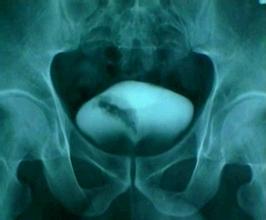

四、X线造影检查:

X线造影检查是膀胱癌的检查方法,通过造影可了解膀胱充盈情况和肿瘤浸润的范围、深度。结合肾盂和输尿管造影可了解是否肾积水、输尿管浸润及浸润的程度等。